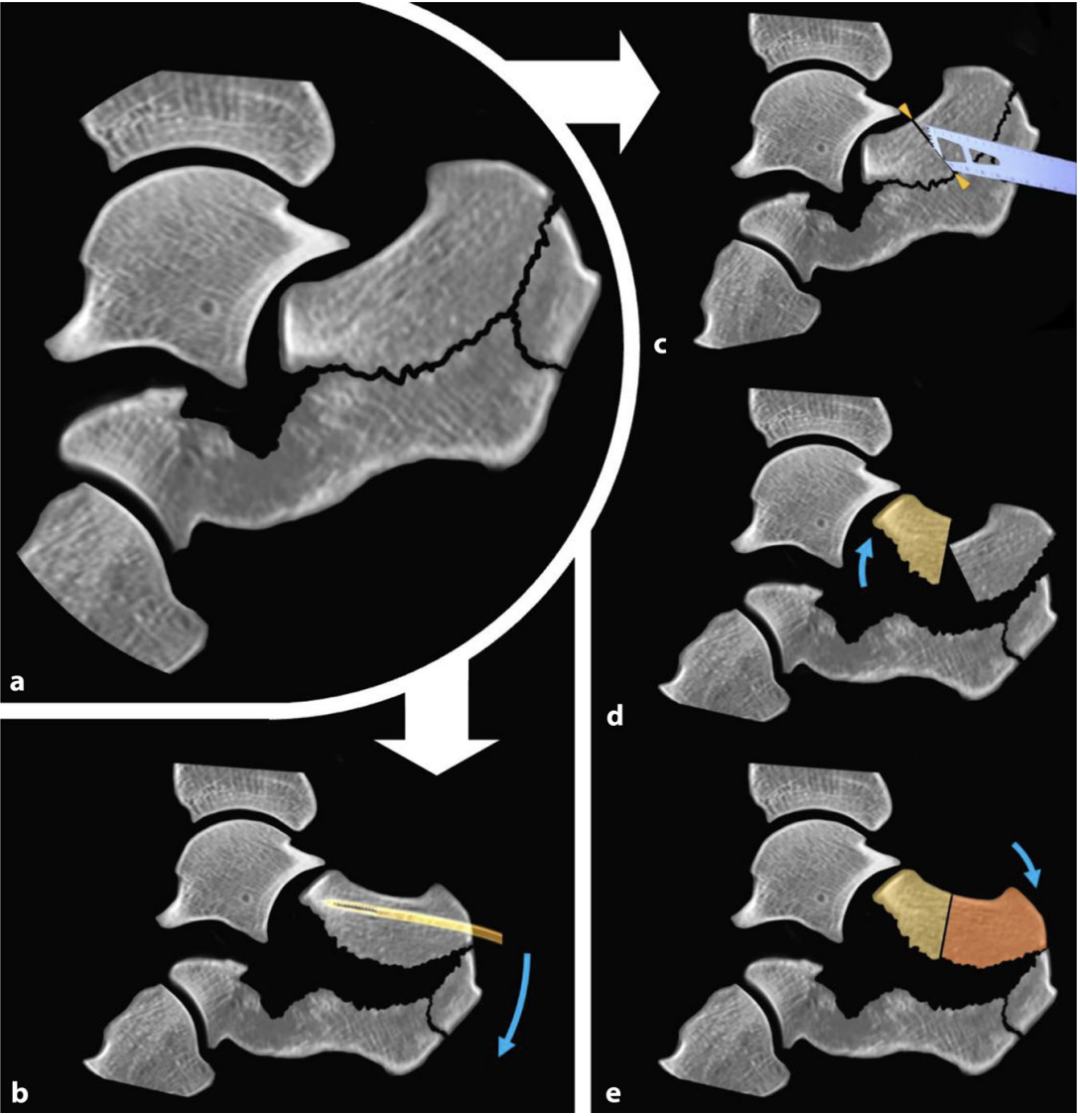

第一步为跟骨结节骨块的牵开复位,该大背侧主骨块通常呈嵌插与外翻畸形。本步骤的目的是解除骨块嵌插,为关节面骨块的操作创造无阻碍的复位空间。

借助经皮置入的带 T 型手柄的斯氏针,采用摇杆技术对跟骨结节骨块进行可控操作,术中可将Böhler角的矫正情况作为复位参考指标。复位后的跟骨结节骨块需用克氏针临时固定于通常较为稳定的内侧载距突骨块(恒定骨块)。亦可采用骨撬进行复位,沿骨折线置入骨撬,沿骨折缝隙轻柔撬拨,精准松解并将跟骨结节复位至内侧壁。

步骤 2:距下关节面的重建

将外侧膨出的薄骨块(“外侧膨出骨块”)像门扉一样掀开,可改善距下关节的显露视野。

关节面的复位以恒定骨块为参照,该骨块为内侧载距突骨块,因与距骨存在韧带连接,通常保持解剖位置,是距下关节后关节面重建的参照标准。若该骨块与距骨关节面贴合不佳,应先对其进行复位,并通过足底经皮置入克氏针将其固定于距骨。

随后,将关节面骨块由内向外逐步贴合恒定骨块进行复位重建,利用细骨撬检查骨块的高度、关节面的对合情况及骨折块的旋转角度是否正常。

对于 SandersⅢ 型或 Ⅳ 型复杂粉碎性骨折,若存在一个或多个中央关节骨块,可采用由内向外逐步重建的方法:从外侧向内侧钻入一枚双头尖克氏针,使克氏针外侧端与骨折面平齐,无针尾突出;外侧骨块复位后,将克氏针从内侧向外侧逆行钻出,贯穿固定外侧骨块。

部分病例中,如关节内骨折线走行不规则,需对移位骨块进行离体重建:将中央关节面骨块与外侧关节骨块取出,在无菌手术台上清理骨块,在直视下完成解剖复位,随后将重建后的关节骨块重新置入术区,精准贴合恒定骨块进行复位。该技术即使对于显露困难或不稳定的骨折块,也能实现可控、解剖学的关节面重建。

对于移位明显的舌型骨折,跟腱的牵拉会增加关节面解剖复位的难度。此类病例中,可采用Essex-Lopresti手法,将 2 枚粗克氏针置入支撑关节面与跟腱止点的舌型骨块,通过向远侧旋转的摇杆动作直接复位骨块。若上述手法复位失败,可在关节面背侧对舌型骨块行冠状面截骨,先复位关节面,再复位跟骨结节骨块。